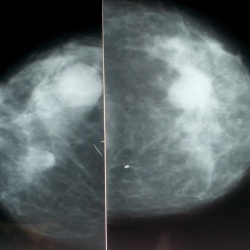

Женщина 49 лет с жалобами на образхования обеих молочных желез. Помогите сформулировать правильное заключение. Могут ли быть множественные фиброаденомы? В литературе не нахожу.